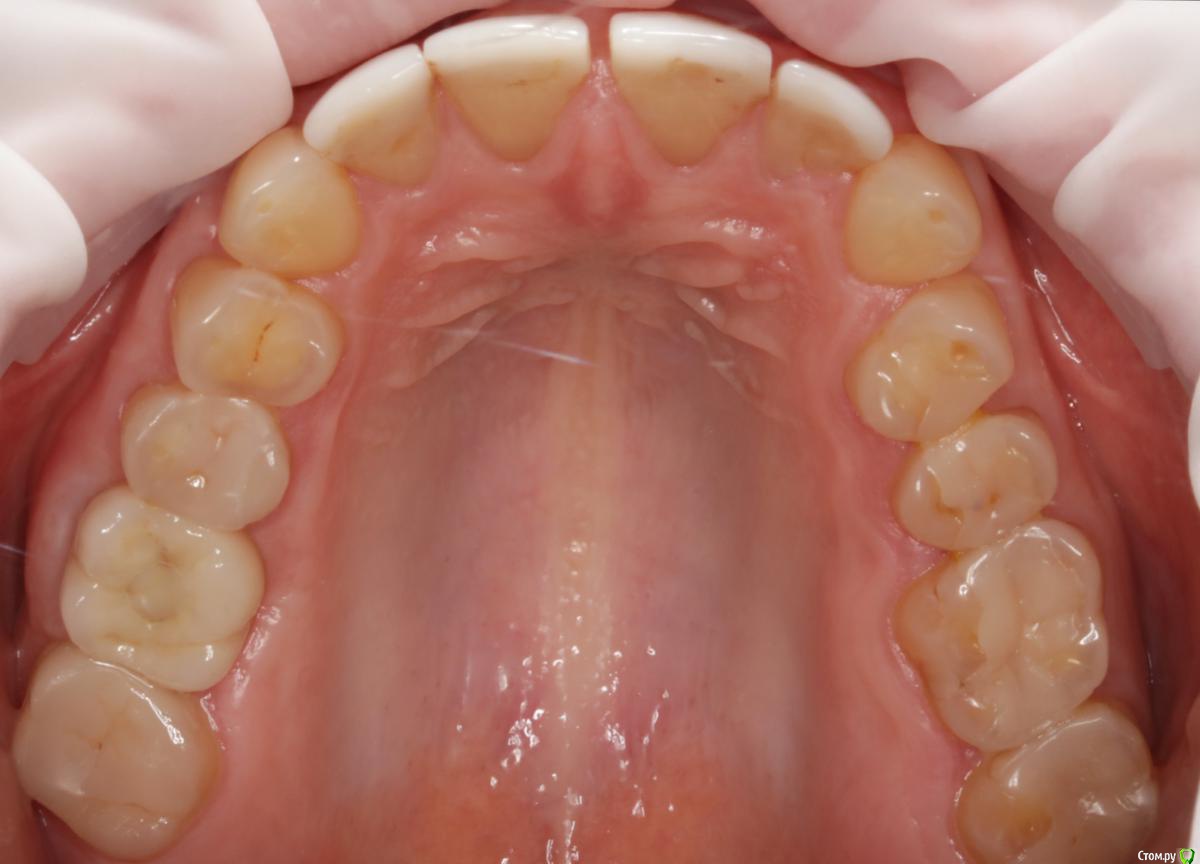

Dmitry DK Опубликовано 10 сентября, 2019 Поделиться Опубликовано 10 сентября, 2019 Фотопротокол к сожалению не полный, но ничего особенного и не проводилось. 1) Открытый синус, удален пломбировочный материал из пазухи, уложен 1 г Bio-oss 2) через 6 мес имплантация Straumann SP 4.1\10 Результат через год 9 Ссылка на комментарий